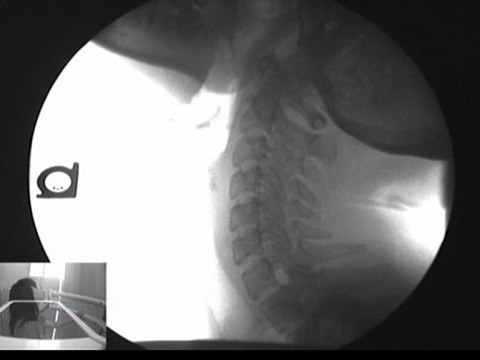

Herniated disc? Pinched Nerves? Low Back Pain? <br /><br />Get out of pain naturally! Call 360-798-4175 for an appointment today. Fast relief from back pain, headaches, and neck pain! Our office, DMX of Vancouver, concentrates on low back pain using the DRX 9000. We use cutting edge diagnostic and treatment machines to get you better

Cutting My Low Back Open for Surgery